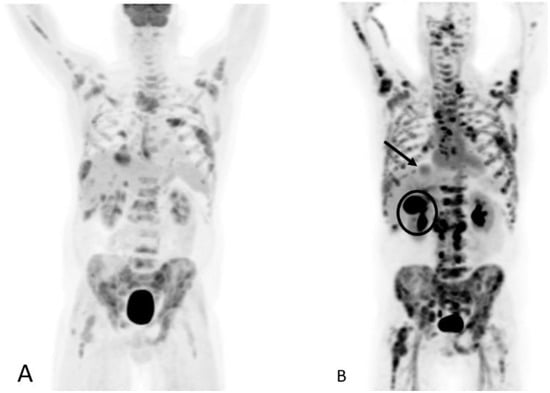

Detection of Loco-Regional Disease and Distant Metastases